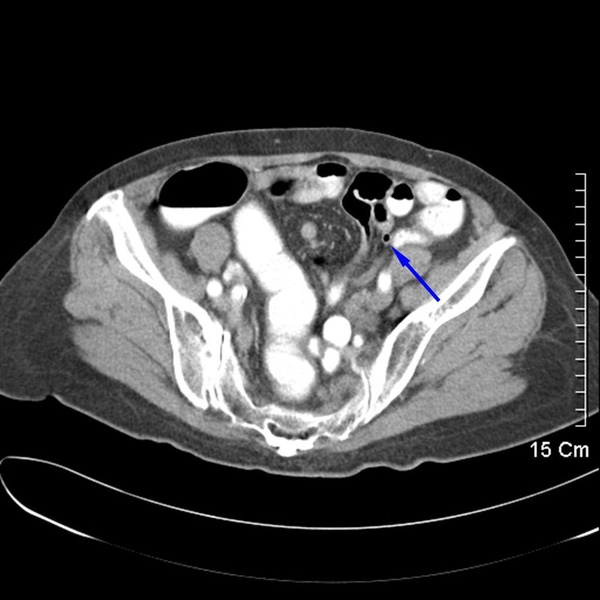

這是種另類的闌尾炎。這是位接受過腎臟移植的患者,藍色箭頭處是移植而來的腎臟,闌尾躲在腎臟下方,又給診斷及手術增添了許多難題。